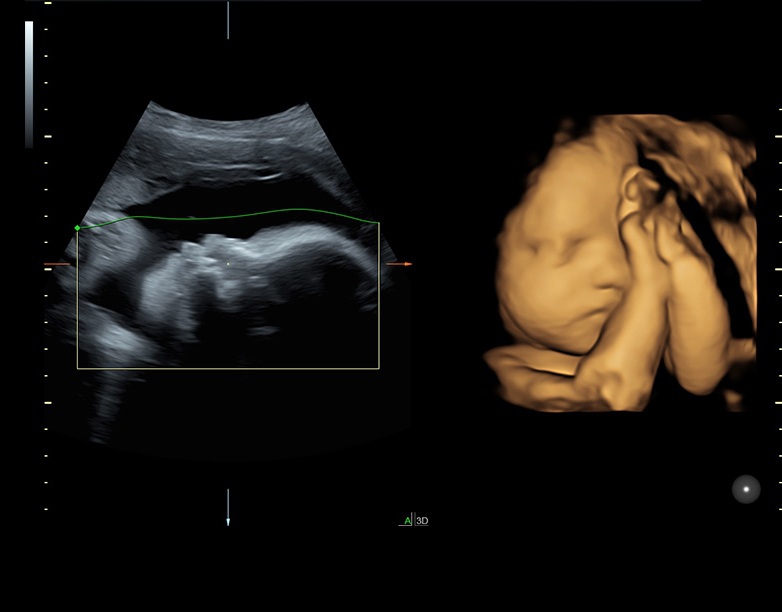

Ультразвуковая платформа Voluson S8 представляет собой оборудование экспертного класса с передовыми возможностями и высоким уровнем автоматизации процессов. Она позволяет проводить сканирование в режимах 2D, 3D и 4D с высоким качеством изображений.

Аппарат Voluson S8 базируется на надежной платформе VCA, которая имеет множество положительных отзывов. Она обладает высококонтрастной технологией объемной реконструкции, обеспечивая качественное воспроизведение изображений. Информация выводится на широкоформатный цветной монитор размером 23 дюйма для убедительной демонстрации плода будущим родителям и облегчения работы врача.

• Технология SonoRenderlive: Эта технология облегчает получение 3D/4D изображений путем автоматического изменения положения плоскости визуализации в зависимости от движений плода. Она позволяет получить реалистичные и объемные изображения, что полезно для демонстрации плода будущим родителям и для дополнительного анализа.